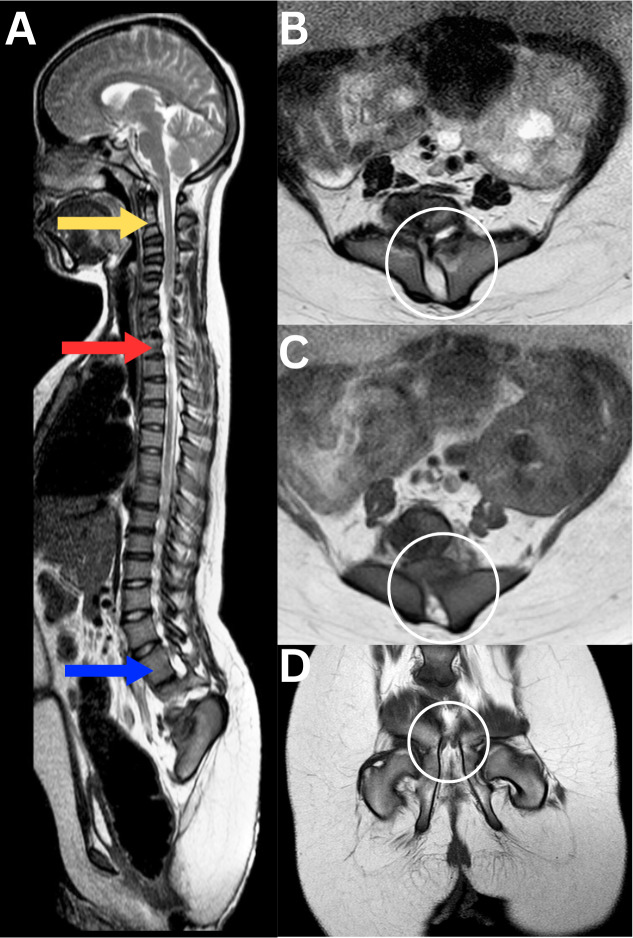

The Impact of Maternal Diabetes on Sacral Agenesis: A paediatric report.

产妇糖尿病对骶骨发育不全的影响:一份儿科报告。